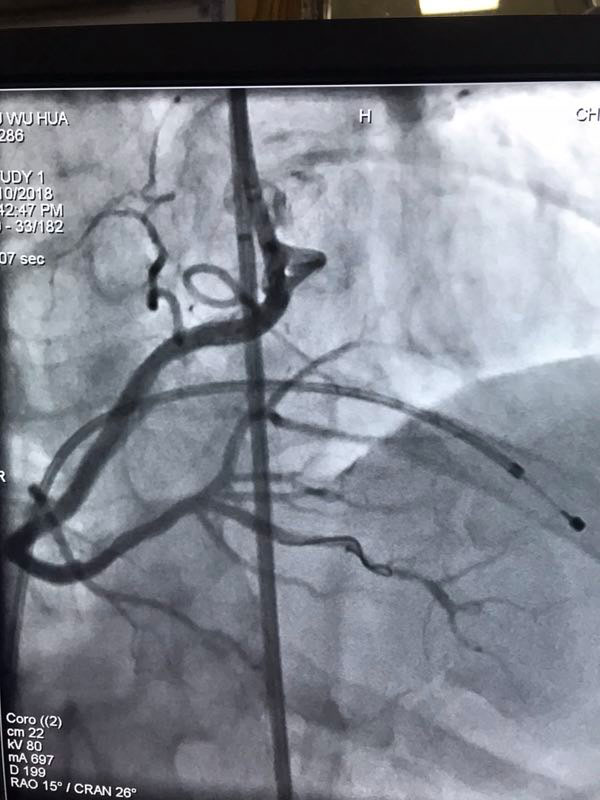

据了解,三位患者都是因严重心绞痛和非ST心梗入院,最高年龄88岁,另两名也有70多岁,是普通PCI难以治疗的危重患者。其中两名已辗转多家医院,均未得到有效救治。患者转入我院后,我院心内科在吴迪主任的带领下,经过周密的准备和科学评估,在血管内超声和临时起搏的辅助指引下,圆满完成了三台旋磨加PCI手术,术后IVUS显示治疗部位支架充分覆盖贴壁,彻底解决了三位患者的病痛,改善了长期预后。

据吴迪主任介绍,冠脉钙化病变和慢性闭塞病变一直是冠心病介入治疗的两大难题,特别是占20%比例的钙化病变,极大的难度风险及高并发症低成功率对心脏介入医生而言是巨大的壁垒和挑战。冠脉旋磨技术作为国家临床二类新技术,就是针对复杂严重钙化病变,通过特制的金刚石探头,在导丝指引氮气加压推进下送入冠脉,借助每秒高达17万转的高速旋转将钙化部位磨平断开,然后借助切割球囊分解斑块,为最终顺利植入支架创造条件。